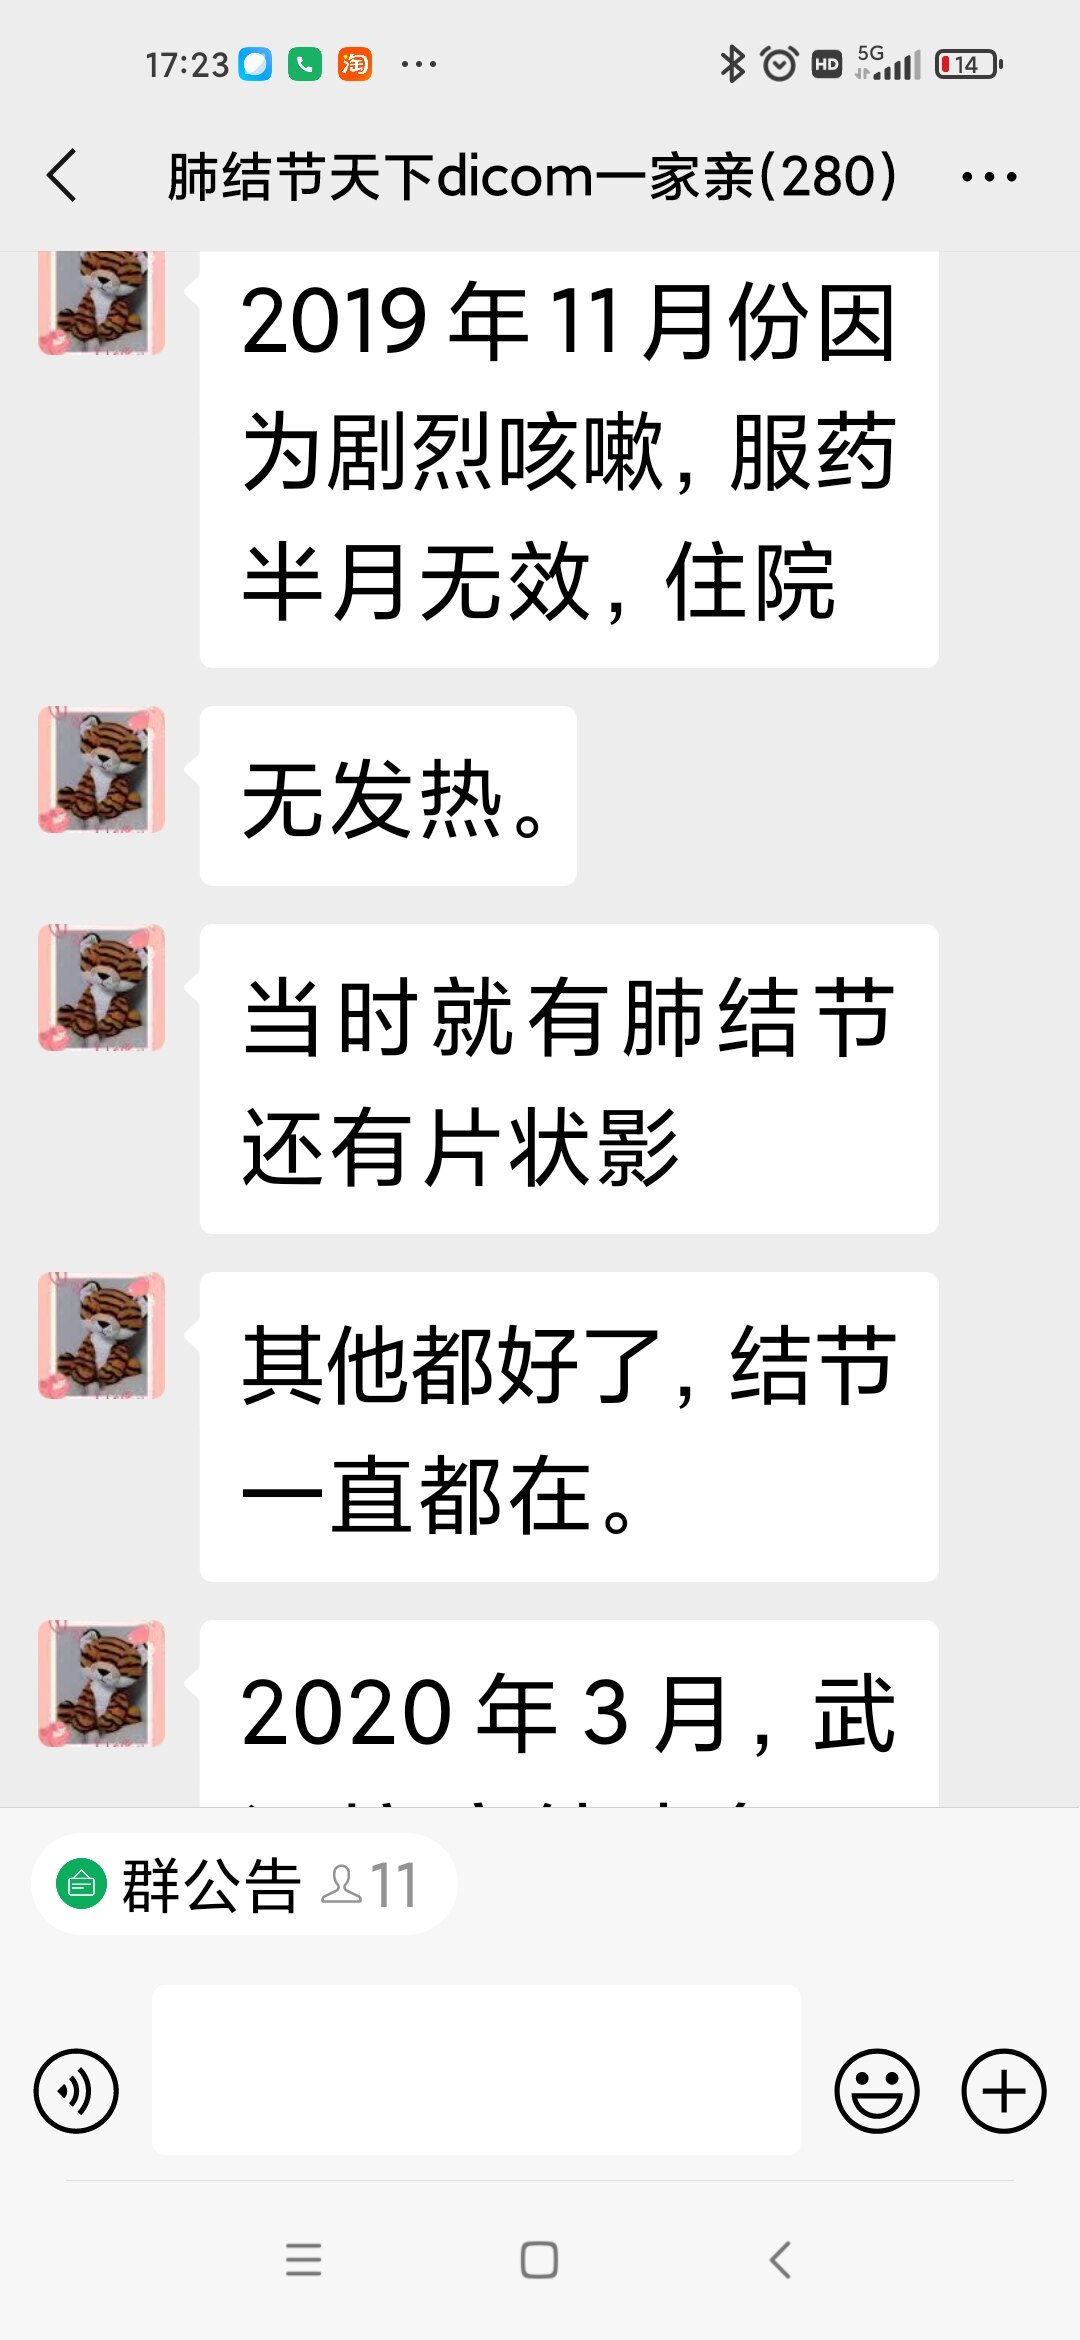

谭先华

副主任医师

武汉市第五医院

放射科

只言片语 之 (7)